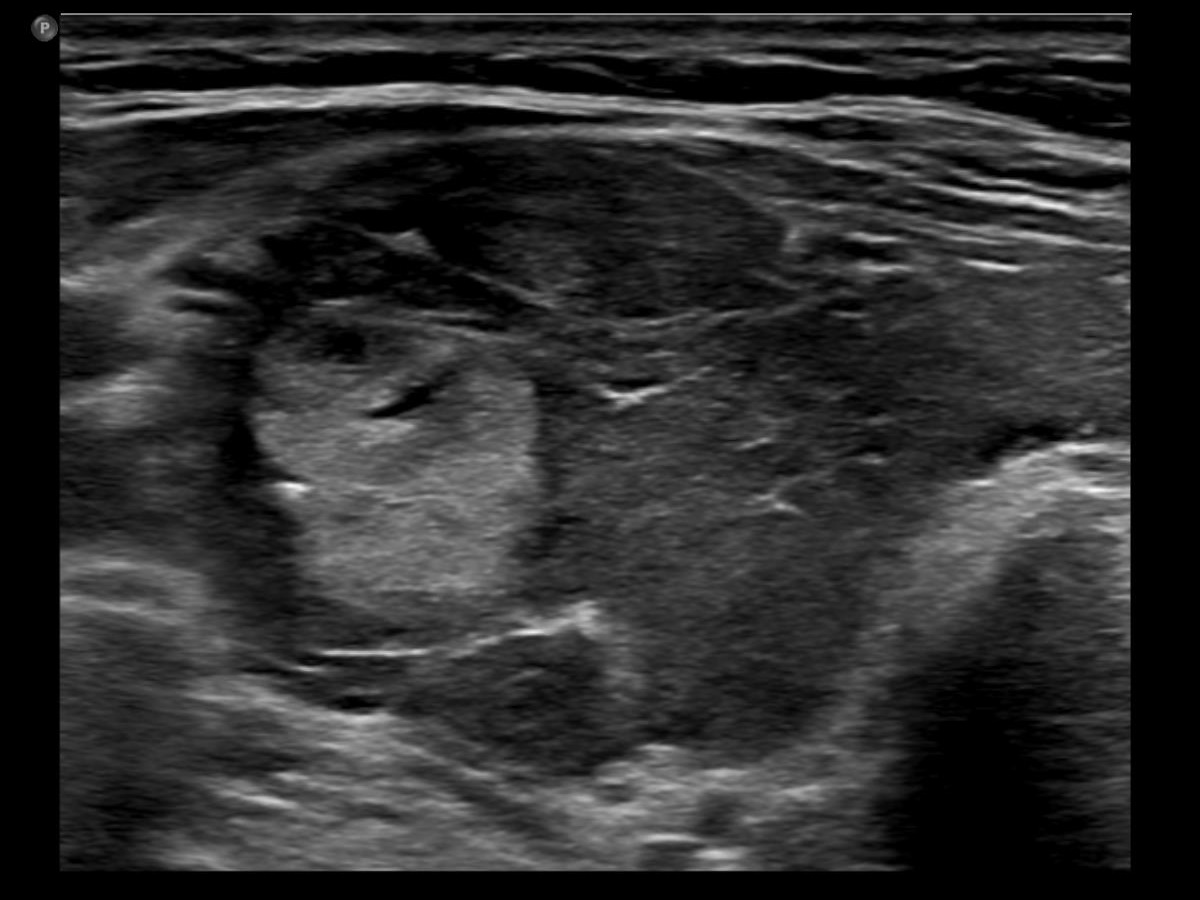

One year after the first examination (second row of images):

Clinical presentation. The patient had no complaints She came to follow-up visit.

Palpation: unchanged.

Results of blood tests: subclinical hyperthyroidism on daily 10 mg methimazole (TSH 0.001 mIU/L, FT4 13.8 pM/L, TSAb 8.2 U/L (normal value below 1.5)).

Ultrasonography. The thyroid became more hypoechoic while the lesion in the central part of the right lobe did hyperechoic. The vascularization of the thyroid was extremely increased.The patient was told that it is very likely that her hyperthyroidism will relapse therefore we suggested radioiodine therapy.